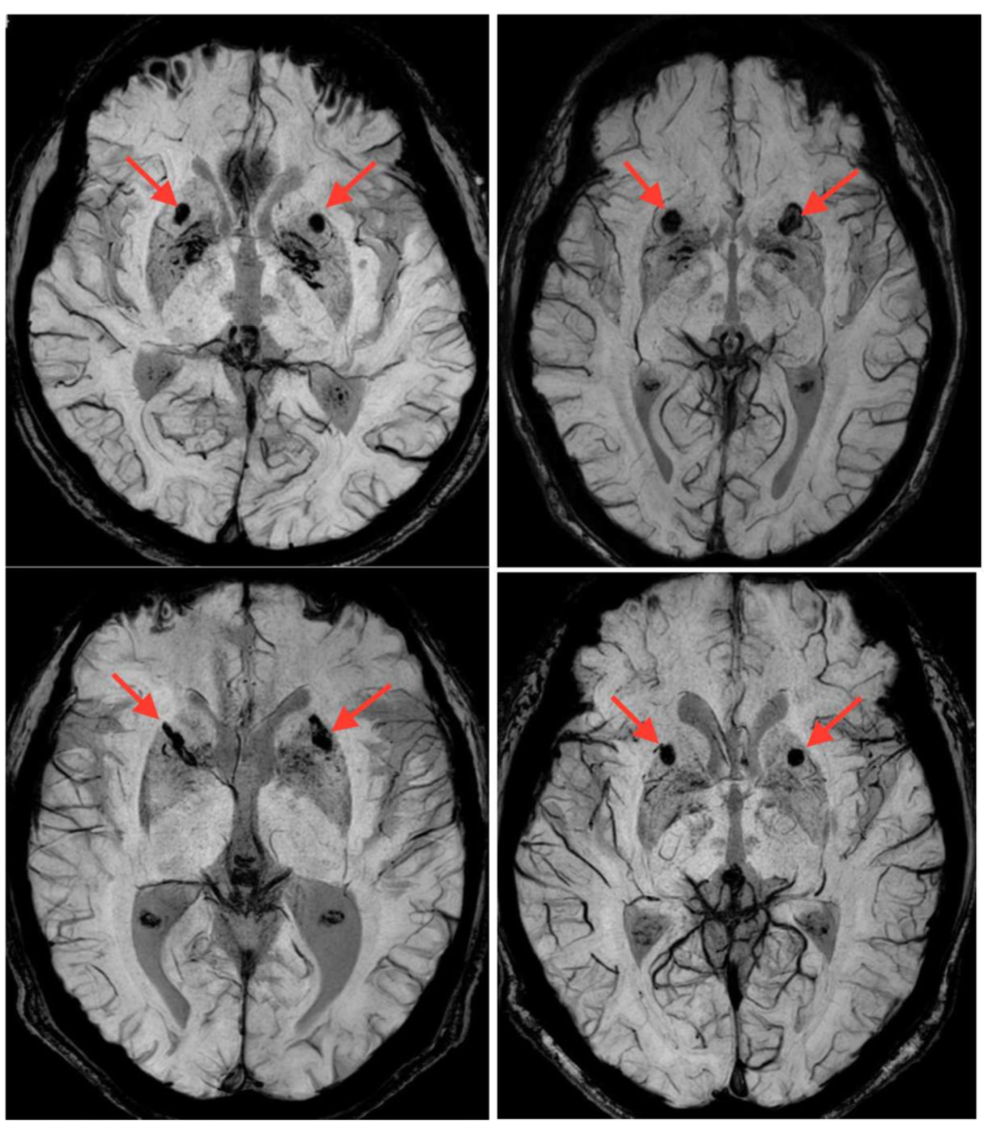

研究人员设计出了一种多孔微型“胶囊”,每个胶囊可容纳1000个猪脑细胞。它的作用在于,能够使猪脑细胞分泌的生长因子渗透到周围的脑组织里,同时保护猪脑细胞不受患者免疫细胞的攻击。

在初次试验中,研究人员为每名患者的一侧大脑植入了40个胶囊。结果发现,在帕金森病严重程度评估体系中,4名患者的病情平均好转了14分(199分制)。而通常情况下,如果不加干预,病情会日益恶化。

进行手术18个月后,根据受试者的主观感受,帕金森的各项症状都得到了改善。最重要的是,没有发现患者因此变蠢,对患者的IQ测试也证实了这一点。